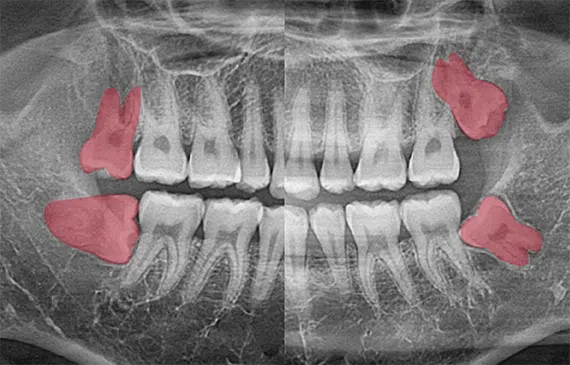

사랑니는 우리 입속에 가장 뒤에 난 어금니를 말하며, 전문용어로 설명해 드리면 제3대구치라고 하며 얼굴을 중심으로 좌우로 8번째 자리하고 있는 치아를 말합니다. 사랑니는 사춘기 이후에 자란다고 합니다. 사춘기에는 여러 가지 감정을 느끼게 되고 그 감정 중 하나가 사랑이라는 감정이지요. 그래서 이 치아를 사랑니라고 부른다고 합니다.

치과 치료를 하면 알 수 있는 것이 치아는 함부로 뽑지 않습니다. 정말 최대한 살려보고 그래도 안 되면 뽑아서 임플란트 등으로 빈자리를 채웁니다. 사랑니는 다른 치아들과 달리 발치를 해야 할 때도 있습니다. 잘 자란 사랑니는 특별한 문제를 일으키지 않아 뽑지 않아도 됩니다. 하지만 대부분의 사랑니는 말썽을 부립니다. 출혈, 염증, 통증 및 악취, 충치 들 여러 가지 문제를 일으킬 확률이 높기 때문에 뽑아야 합니다.